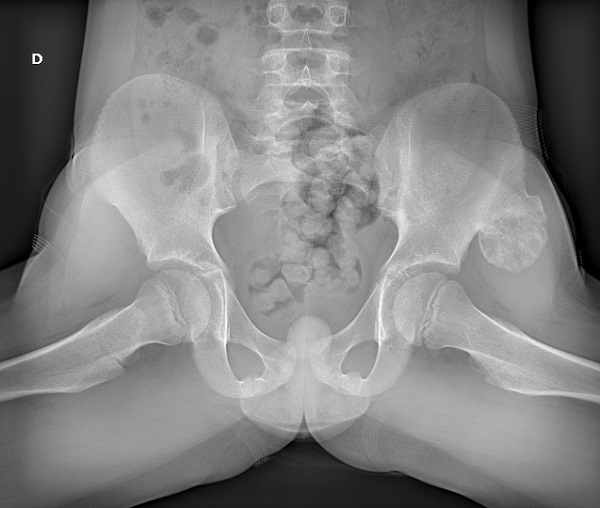

Se realiza radiografía de pelvis en proyecciones AP y axial, apreciándose a nivel de la pala ilíaca izquierda lesión excrecente de 46 x 33 mm, con componente óseo y amplia base y matriz condral compatible con osteocondroma.